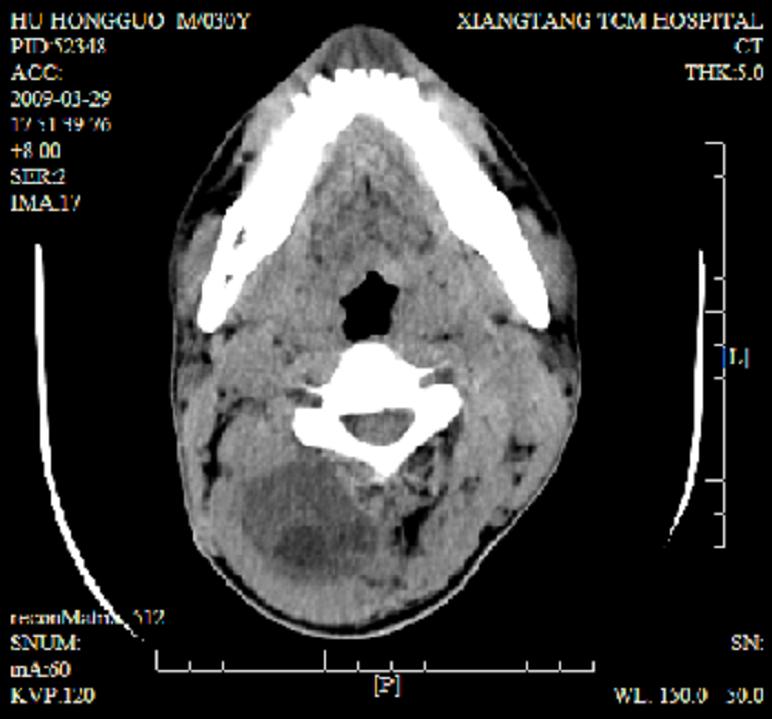

标题: CT19102:颈部肿块

男30y发现肿块3年

多处囊实性肿块,形态欠规则有一定形态,内见点状钙化,以囊变为主,增强后轻度强化,首先考虑神经源性肿瘤如鞘瘤,不除外脉管源性肿瘤如淋巴管瘤(见缝钻及囊性区域太多,如果合并感染完全可以这个影像表现),和海绵状血管瘤,但是血管瘤不太支持因为强化特征和病灶形态不典型.

右侧椎前间隙后部肌间、皮下囊性为主病变,可见分隔和点状钙化,分隔和壁呈轻度环形强化,大部分无强化。形态不规则,有钻缝特点。考虑1 淋巴管瘤合并感染2 血管平滑肌脂肪瘤3 表皮样囊肿4 不除外海绵状血管瘤。

病灶沿皮下及肌间隙爬行,病灶内有钙化灶,病灶有强化。病史3年,病人应该没什么症状。考虑纤维血管瘤可能性大。